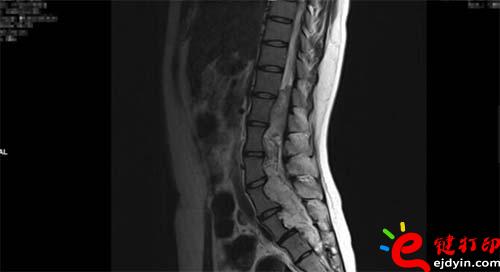

【VR和3D打印在微創椎管內硬膜下先天性腫瘤切除術中的應用】近日,山西省人民醫院成功完成一例微創通道胸12-骶2椎管內硬膜下先天性腫瘤切除術手術,在手術前醫院使用了西安鑫威泰科技自主研發的傲視虛擬現實數字醫療系統和3D打印模型進行手術規劃,制定手術方案,對本次手術的成功起到了至關重要的作用。